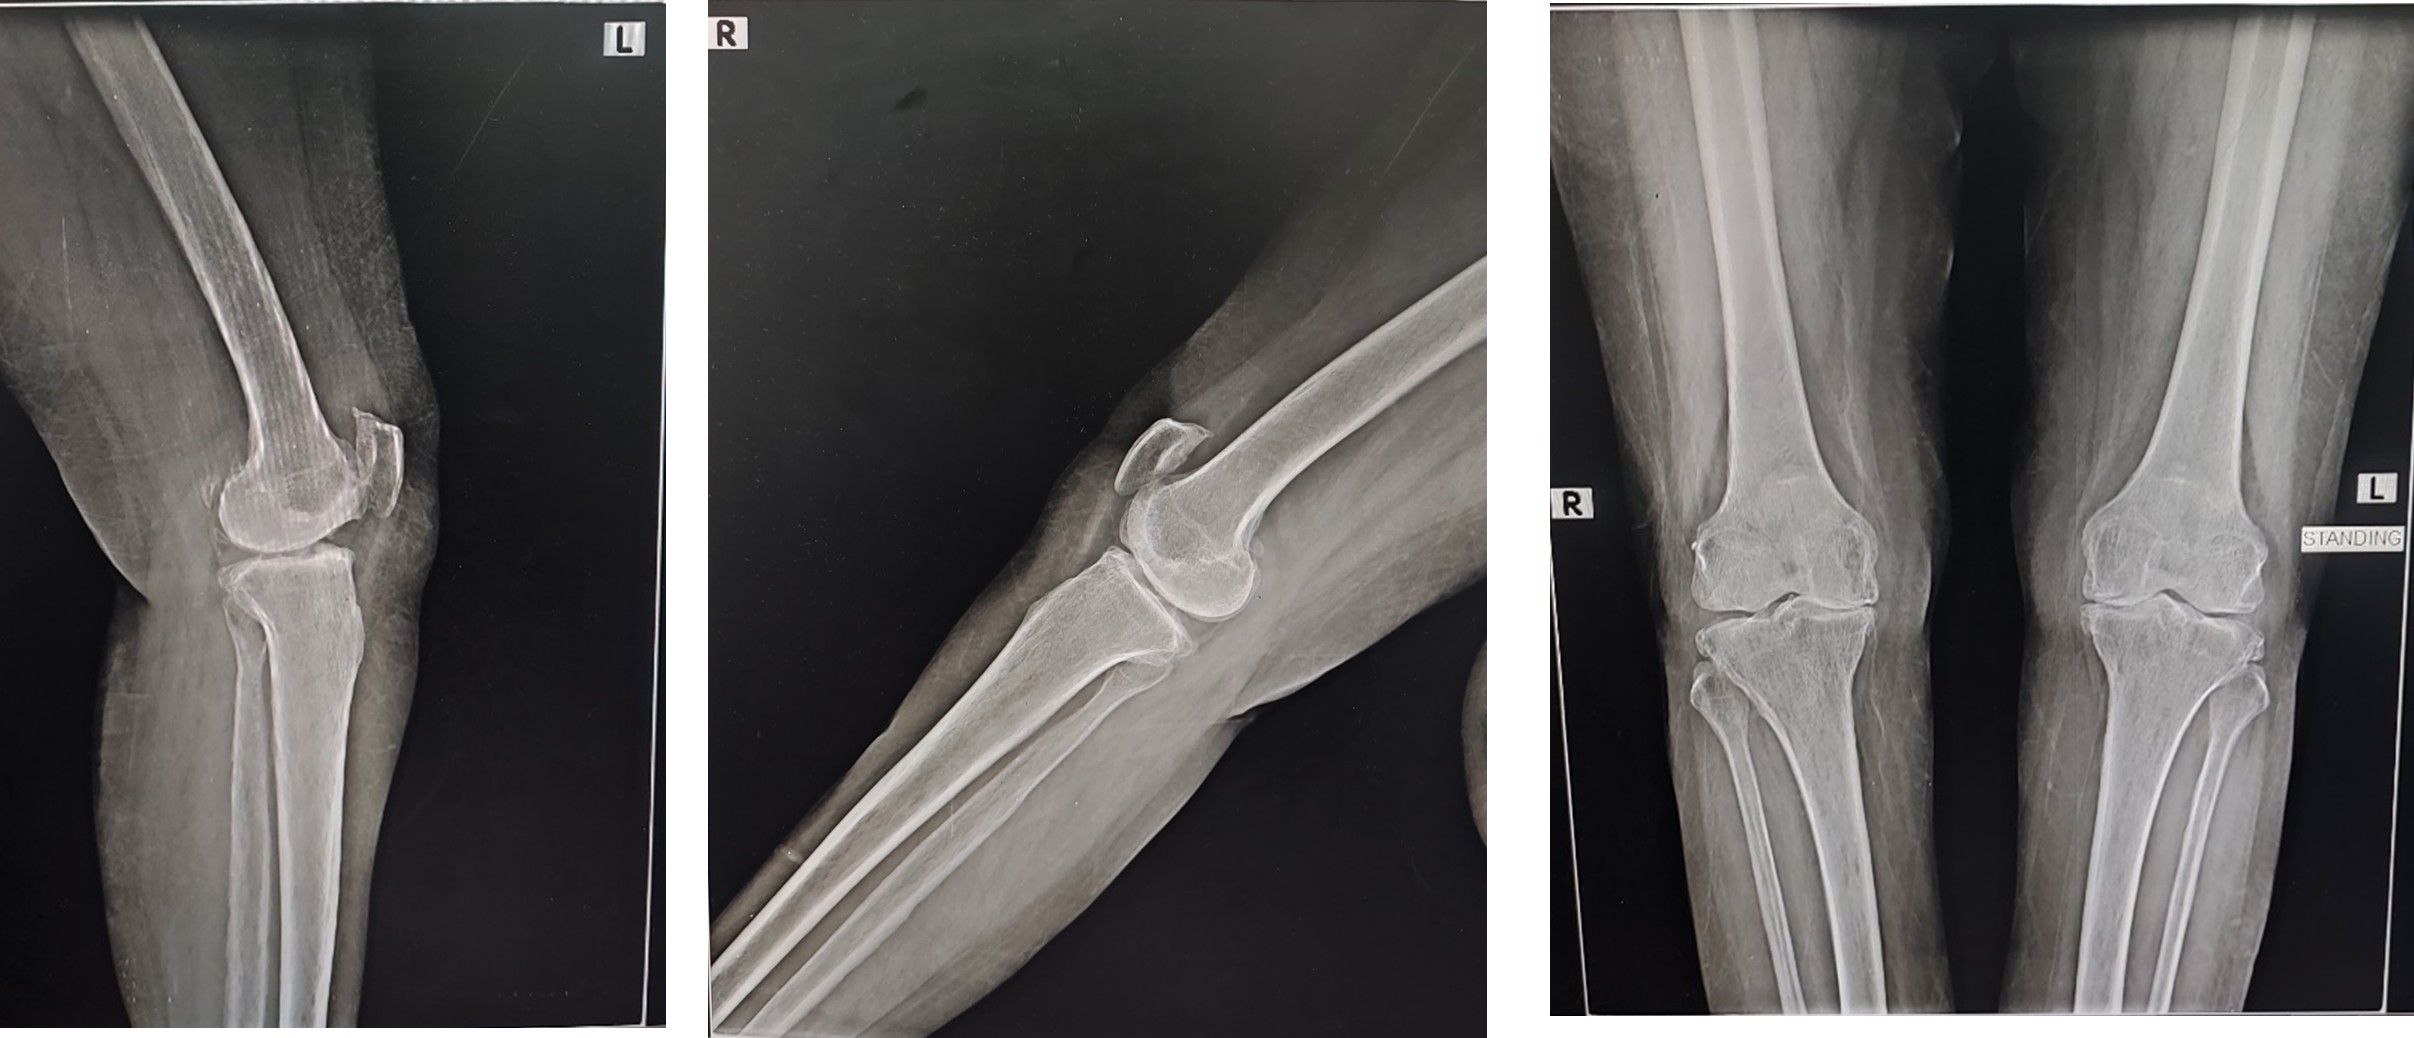

Preoperative X-ray

- Case presentation on Total Knee Replacement